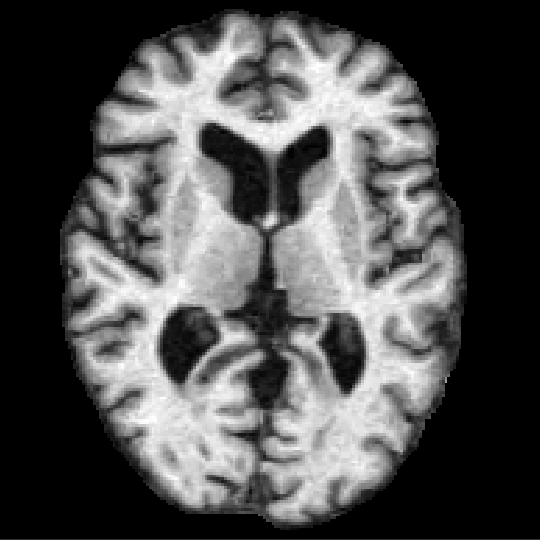

CuRIOUS Hippocampus MR Abdomen CT-CT

Fixed Moving Fixed Moving Fixed Moving

[Uncaptioned image] [Uncaptioned image] [Uncaptioned image] [Uncaptioned image] [Uncaptioned image] [Uncaptioned image]

Modalities MR T1w & FLAIR/US MR T1w/MR T1w CT/CT

Intra-/Inter-patient Intra-patient Inter-patient Inter-patient

Resolution 256×256×288256256288256{\times}256{\times}288 64×64×6464646464{\times}64{\times}64 192×160×256192160256192{\times}160{\times}256

Voxel size 0.5×0.5×0.5 mmsimilar-toabsent0.50.50.5timesabsentmillimeter{\sim}0.5{\times}0.5{\times}0.5$\text{\,}\mathrm{mm}$ 1×1×1 mm111timesabsentmillimeter1{\times}1{\times}1$\text{\,}\mathrm{mm}$ 2×2×2 mm222timesabsentmillimeter2{\times}2{\times}2$\text{\,}\mathrm{mm}$

Cases (Train/Test) 22/10 263/131 30/20

Preprocessing resample crop/pad/resample canonical affine pre-align

crop/pad/resample

Annotations (Train/Test) –/9-18 landmarks/case 2/2 anatomical labels 13/13 anatomical labels

Additional data

Metrics TRE/TRE30 DSC/DSC30/HD95 DSC/DSC30/HD95

SDlogJ/RT SDlogJ/RT SDlogJ/RT

TABLE I: Overview of all six Learn2Reg tasks addressing the imminent challenges of medical image registration: multi-modal scans \mathbin{\vbox{\hbox{\scalebox{2.0}{$\bullet$}}}} (tasks with at least two different image modalities), few/noisy annotations \mathbin{\vbox{\hbox{\scalebox{2.0}{$\bullet$}}}} (less than five annotated anatomical structures for training cases), partial visibility \mathbin{\vbox{\hbox{\scalebox{2.0}{$\bullet$}}}} (restricted or cropped field of view for at least one image of a registration pair), small datasets \mathbin{\vbox{\hbox{\scalebox{2.0}{$\bullet$}}}} (less than 30 training cases), large deformations \mathbin{\vbox{\hbox{\scalebox{2.0}{$\bullet$}}}} (tasks with initial displacements of at least 10 cm10timesabsentcentimeter10$\text{\,}\mathrm{cm}$), small structures \mathbin{\vbox{\hbox{\scalebox{2.0}{$\bullet$}}}} (tasks containing cases with target structures comprising less than 100 voxels), unsupervised registration \mathbin{\vbox{\hbox{\scalebox{2.0}{$\bullet$}}}} (no annotations for training cases) and missing correspondences \mathbin{\vbox{\hbox{\scalebox{2.0}{$\bullet$}}}} (e.g. due to removed organs, different field of views etc.)

.

OASIS

The task employed 416 3D whole-brain MR scans from the Open access series of imaging studies (OASIS) [30], a cross-sectional MR data study with a wide range of participants from young, middle-aged, nondemented, and demented older adults. The clinical relevance of this inter-patient registration task lies in quantitative brain analysis, which is of utmost importance for a better understanding of the human brain and for the analysis of various brain diseases. Standard brain MR pre-processing including skull-stripping (optional), normalisation, pre-alignment, and resampling was performed. Semi-automatic labels with manual corrections of 35 cortical and subcortical brain structures were generated using FreeSurfer [31]. For details on data curation, see [32].